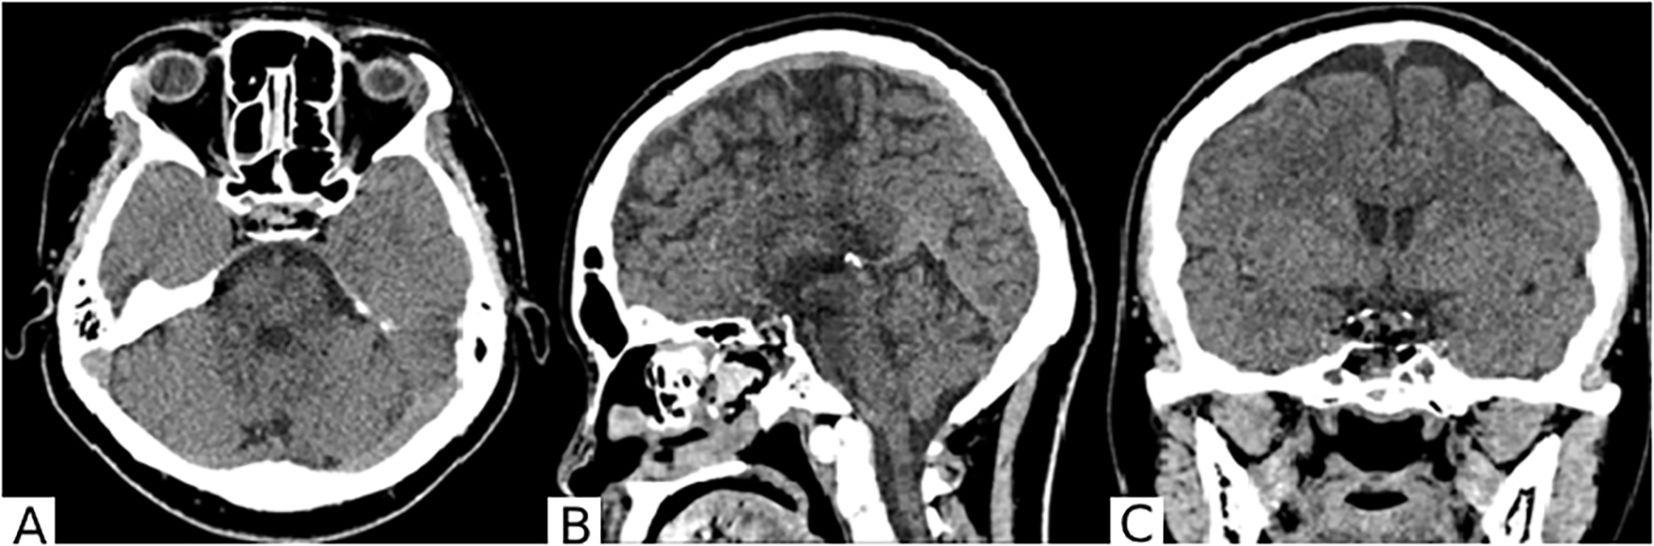

The surgery was performed without complications. The patient was observed for the first 20 hours in the intensive care unit of anesthesiology and resuscitation, followed by transfer to the specialized neurosurgical department. No complications were observed in the postoperative period. A follow-up CT scan of the brain was performed on the first postoperative day (Figure 4).

Figure 4. On the brain CT scan in axial (A), sagittal (B), and frontal (C) projections after surgery, the surgical site in the chiasmal-sellar region is visible. A small hemorrhagic component is present in the main sinus. The lateral III-IV ventricles are not enlarged. Extracerebral cerebrospinal fluid spaces are unremarkable.